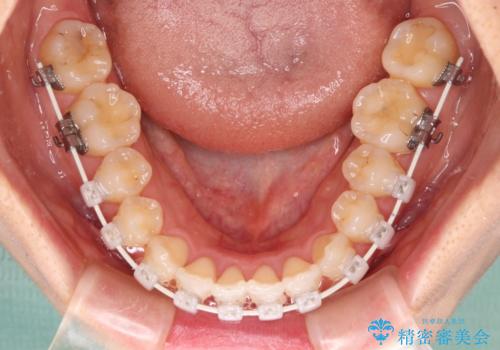

- 審美装置

- 11ヶ月

- 10-30回

矯正治療中に上下前歯が接触しない時期があり、咬み合わせ改善のために期間がかかるのではないかと懸念されましたが、結果的には補綴治療も含めて1年以内の短期間で終えることができました。